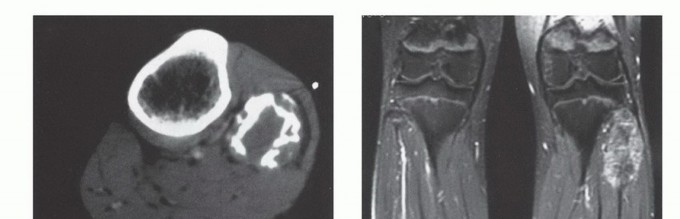

التصوير بالرنين المغناطيسي (MRI): يُعد MRI الأداة الأكثر قيمة لتقييم أورام العظام. يوفر صورًا مفصلة للأنسجة الرخوة المحيطة بالعظم (العضلات، الأوتار، الأعصاب، الأوعية الدموية)، ويحدد مدى انتشار الورم داخل العظم وإلى الأنسجة الرخوة المجاورة. وهو ضروري للتخطيط الجراحي للحفاظ على الطرف.

التصوير المقطعي المحوسب (CT Scan): يوفر صورًا تفصيلية لبنية العظم بدقة عالية، ويكشف عن تآكل القشرة العظمية، وتكوين العظم الجديد، وتكلسات الورم. كما يستخدم للكشف عن أي انتشار للورم إلى الرئتين (نقائل).